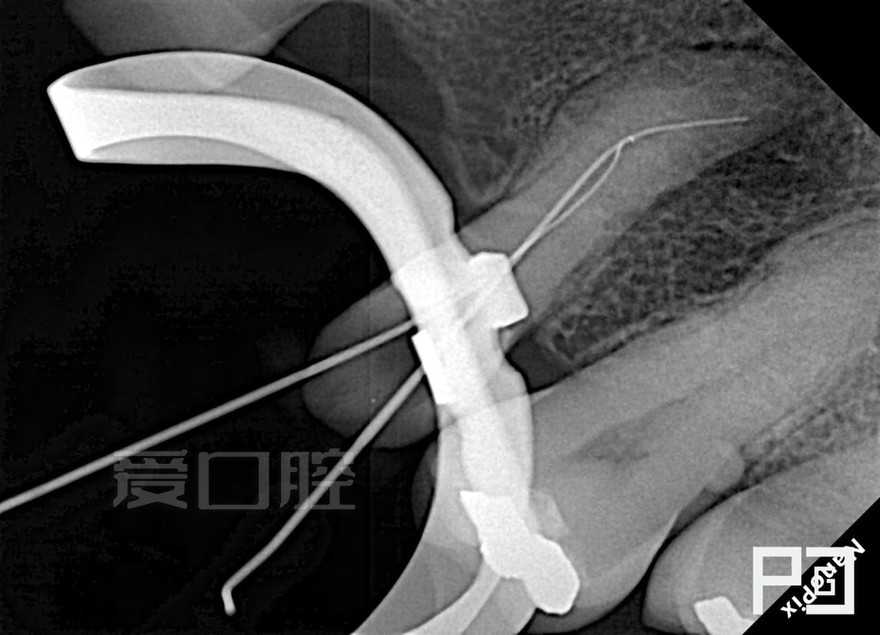

看个根充 —— 上5

by Paco CG